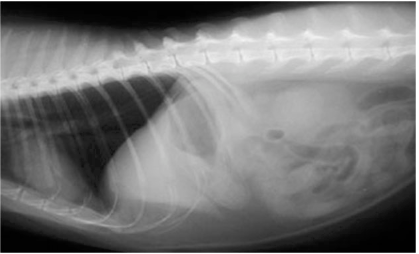

This is a lateral radiograph of the caudal abdomen of a dog.

Which statement best represents the reason why this dog requires immediate surgery?

There is a soft tissue opacity ventral to the caudal vertebrae containing a loop of small intestine: indicative of a perineal hernia with entrapped small intestine